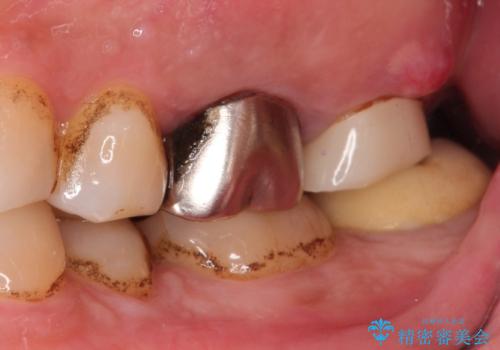

【歯牙破折】インプラントによる咬合回復

- 痛みを主訴に来院されました。

歯牙の破折を認めたため抜歯をし、インプラントにて咬合回復をしました。

抜歯後、骨増生を行ったのちインプラントを埋入しています。